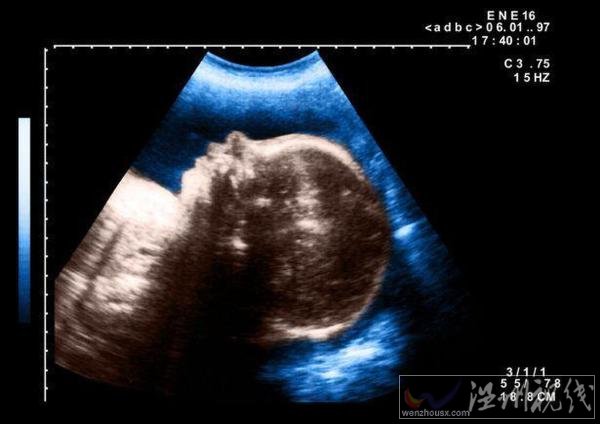

10月7日,埃及一名孕妇产下一个独眼婴儿,这个孩子在出生几天后死亡。埃及婴儿一只眼睛一时引起不少人关注,这名医生猜测,可能是婴儿在子宫内受到放射物影响导致的畸形。

据悉,当时这名医生在被这个孕妇做检查时,就发现她怀的这个孩子是一个严重畸形儿,但是没想到会是这样的。这个婴儿出生时,只有一只长在中间的眼睛,在眼睛下面就是一张嘴巴。

医生在对其做完接生后预计这个孩子活不过几天,对于孩子畸形的原因,他认为应该是受到放射物质影响。